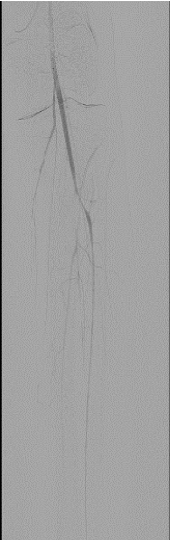

The right leg was targeted next. It had proximal PFA occlusion and distal below the knee occlusion and the access was obtained from the left common femoral artery. Occluded proximal PFA and distal popliteal on the right side were confirmed (Figure 7). There were distal collaterals below the knee leading to filling of the anterior tibial artery. The occluded PFA was crossed with a 0.014-inch wire and treated with 4 mm balloon angioplasty catheter but once again with no angiographic improvement with balloon angioplasty. The occlusion was then treated with aspiration thrombectomy using a 6 F Multipurpose guiding catheter with the same technique as on the left leg.  There was increased patency of the PFA as a result of this. The distal popliteal occlusion was similarly crossed with a wire and treated with a balloon catheter. Again, no improvement was seen below the knee using balloon angioplasty and noting the results from the left leg where ultrasound facilitated thrombolysis had yielded good results in achieving vessel patency, overnight Ekos catheter directed thrombolytic therapy was applied with the Ekos catheter tip in the proximal peroneal artery (Figure 8). The patient was noted to markedly improve upon angiographic visualization. The PFA was patent with residual stenotic lesions but looking markedly improved compared to the total occlusion from the day before. The SFA and popliteal were patent and below the knee, there was single vessel run off to the posterior tibial artery that had moderate residual lesions only (Figure 9). Then, the lower extremity procedures were concluded, and the patient no longer had any further leg discomfort. The retrieved pieces from the aspiration thrombectomy on pathological reports were consistent with septic emboli (Figure 10).

Figure 7. Right leg: Filling defect in right distal popliteal artery with collaterals filling the anterior tibial artery